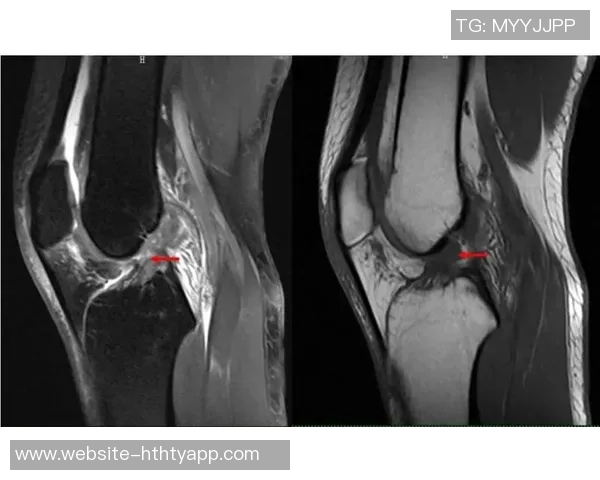

近日,马德里竞技官方宣布,球队后卫朗格莱在比赛中遭遇重度内侧副韧带扭伤,并且幸运的是没有其他损伤。这一消息引发了广泛关注,朗格莱在球队中的重要性不言而喻,他的受伤可能会对球队的后防线造成一定影响。本文将从四个方面详细探讨这一事件,包括朗格莱的个人表现、受伤对球队的影响、康复预期及医疗团队的角色以及球迷和媒体反响。希望通过这些分析,能够更清晰地理解这一事件的重要性及其潜在后果。

根据马德里竞技官方发布的信息,朗格莱虽遭遇重度内侧副韧带扭伤,但幸好没有伴随其他损伤。这意味着他的康复前景相对乐观,但仍需经过一段时间休整和治疗。一般来说,这类伤病恢复需要数周至数月不等,而具体时间还需根据医生评估情况而定。